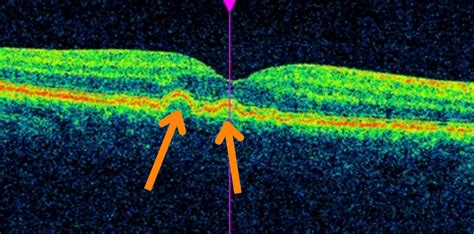

Guys, the new optical experience starts long before you pick out frames. Eye exams have undergone a massive transformation. Forget the old-school eye charts; modern optometry practices are equipped with advanced diagnostic tools that provide a comprehensive look at your eye health. Think high-resolution imaging , 3D retinal scans , and advanced glaucoma testing . These technologies allow optometrists to detect potential eye diseases like macular degeneration, glaucoma, and diabetic retinopathy in their earliest stages, often before you even notice any symptoms. Early detection is absolutely crucial for effective treatment and preserving your vision long-term. Some practices even offer corneal topography to map the surface of your eye, which is essential for fitting specialty contact lenses or identifying conditions like keratoconus. Furthermore, digital eye strain assessments are becoming standard, recognizing the impact of our screen-heavy lifestyles on our eyes. These assessments help in recommending specific lens coatings or lifestyle adjustments to mitigate discomfort and protect your vision from the harmful effects of blue light. The whole process is much more personalized and proactive. It’s about understanding your eyes as a vital part of your overall health, not just a tool for sight. These sophisticated exams ensure that any vision correction prescribed is tailored to your unique needs, taking into account factors like your visual demands at work and during leisure activities. So, when you book your next eye appointment, expect a much more thorough and technologically advanced experience. This commitment to advanced diagnostics is a cornerstone of new optical care, ensuring your eyes are not only seeing clearly but are also as healthy as they can be.